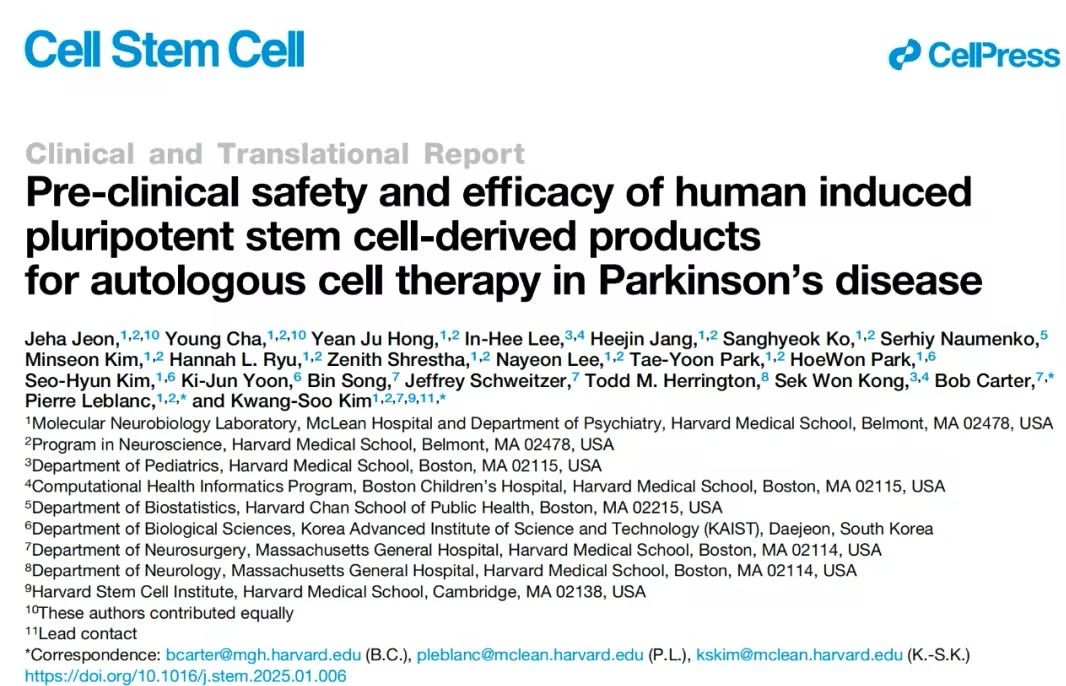

帕金森病(Parkinson’s Disease, PD)是一种常见的神经退行性...